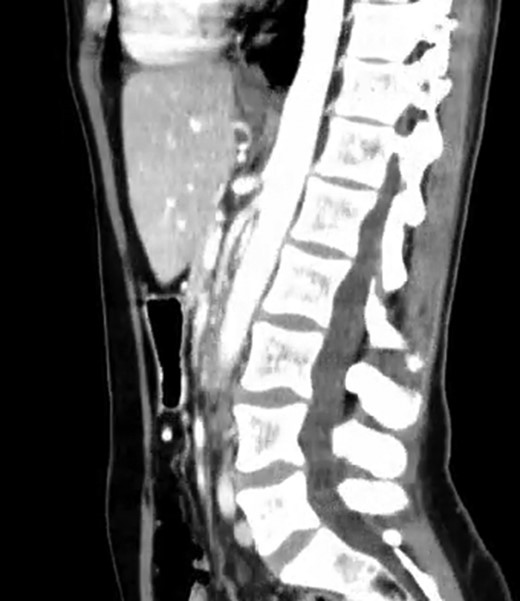

A 39-year-old Caucasian female patient presented to a General surgery outpatient clinic with complaints of epigastric pain, nausea, vomiting and weight loss for more than 5 years. The pain was worse after eating and with supine position. Vomiting was usually initiated 3–4 h after meals and consisted of undigested food. She had no significant prior medical history. On examination, the patient was extremely emaciated, with normal vital signs but with a distended abdomen and fullness over the epigastrium. She had already done an upper endoscopy that only showed gastric stasis. Abdominal ultrasound revealed a reduced angle between the AA and SMA (Fig. 1). An upper GI contrast study was requested, which revealed a distended stomach with delayed gastric emptying and lagging of contrast at the third portion of the duodenum (Fig. 2). Abdominal computed tomography (CT) scan was then performed. It demonstrated a severe distension of the stomach and proximal portions of the duodenum with constriction of the third part of the duodenum between the AA and SMA, with a reduced angle (11°) and shortened distance (4–5 mm) between these two arteries (Figs 3 and 4). These findings were suggestive of an aortomesenteric clamp. Hence, based on known findings, the diagnosis of Wilkie’s syndrome was established.

CT scan—sagittal CT image of reduced angle between AAA and SMA.